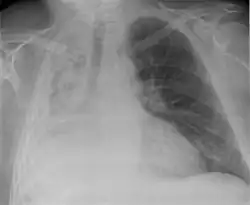

| Atelectasis of a person's right lung | |

Atelectasis is the partial collapse or closure of a lung resulting in reduced or absence in gas exchange. It is usually unilateral, affecting part or all of one lung.[2] It is a condition where the alveoli are deflated down to little or no volume, as distinct from pulmonary consolidation, in which they are filled with liquid. It is often referred to informally as a collapsed lung, although more accurately it usually involves only a partial collapse, and that ambiguous term is also informally used for a fully collapsed lung caused by a pneumothorax.[1]

It is a very common finding in chest X-rays and other radiological studies, and may be caused by normal exhalation or by various medical conditions. Although frequently described as a collapse of lung tissue, atelectasis is not synonymous with a pneumothorax, which is a more specific condition that can cause atelectasis. Acute atelectasis may occur as a post-operative complication or as a result of surfactant deficiency. In premature babies, this leads to infant respiratory distress syndrome.

Clinically significant atelectasis is generally visible on chest X-ray; findings can include lung opacification and/or loss of lung volume. Post-surgical atelectasis will be bibasal in pattern. Chest CT or bronchoscopy may be necessary if the cause of atelectasis is not clinically apparent. Direct signs of atelectasis include displacement of interlobar fissures and mobile structures within the thorax, overinflation of the unaffected ipsilateral lobe or contralateral lung, and opacification of the collapsed lobe. In addition to clinically significant findings on chest X-rays, patients may present with indirect signs and symptoms such as elevation of the diaphragm, shifting of the trachea, heart and mediastinum; displacement of the hilus and shifting granulomas.[13]